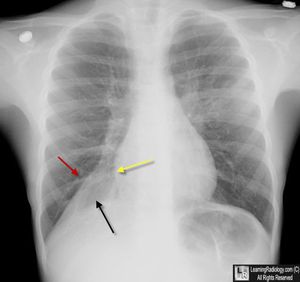

1.bronchectasis 2.emphysema 3.chronic bronchitis 4.pneumothorax caused by bronchial obstruction, usually a tumor (i.e. a bronchogenic carcinoma), a foreign body or a mucus plugIn asthmatics, chronic inflammation along with the thicker and more viscous mucus leads to mucous plugging and impaction